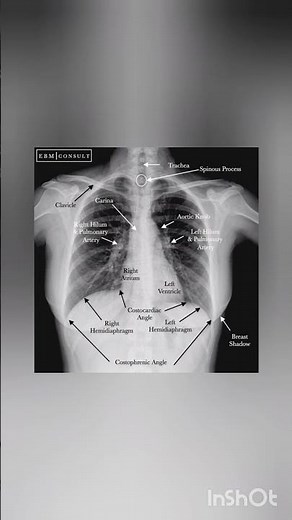

Anatomy - Chest X-ray

X-ray - Chest X-ray